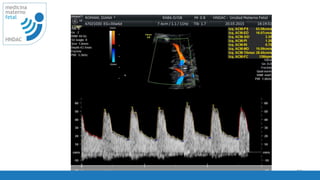

velocidad de barrido

PRF

25

corregido

26